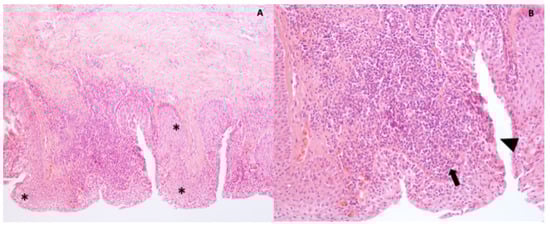

2.8. Histology and Transmission Electron Microscopy